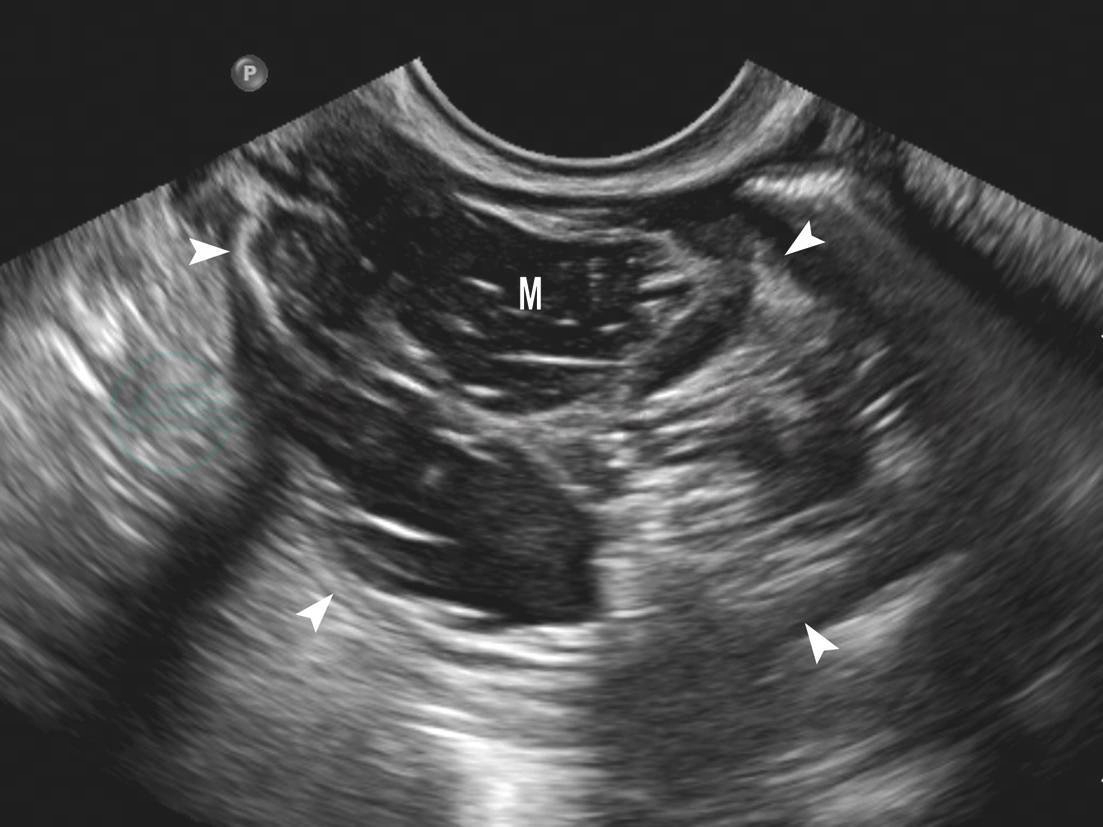

属于卵巢上皮性肿瘤。多数表现为多房囊性肿块,少部分表现为单房性,肿块外形椭圆形,边界清晰,囊内为无回声,囊壁不规则,囊壁光滑。浆液性囊腺瘤以单房、少房居多,黏液性囊腺瘤以多房为主,且瘤体较大(图7-5,图7-6)。乳头状囊腺瘤在瘤内壁及分隔上可见散在的点状、结节状或乳头状凸起,以浆液性囊腺瘤多见(图7-7)。CDFI显示囊壁、囊内间隔以及乳头上可见细条状血流(图7-8),频谱多普勒可记录到低速中等阻力动脉频谱。当分隔较多,血流较丰富时,血流频谱与恶性卵巢肿瘤频谱相似,需注意交界性囊腺瘤可能,但超声较难鉴别。卵巢囊腺瘤病变可呈双侧性,以浆液性囊腺瘤多见。

图7-5 卵巢浆液性囊腺瘤声像

M:卵巢浆液性囊腺瘤;箭头:浆液性囊腺瘤边界

图7-6 卵巢黏液性囊腺瘤声像

M:卵巢黏液性囊腺瘤;箭头:黏液性囊腺瘤边界